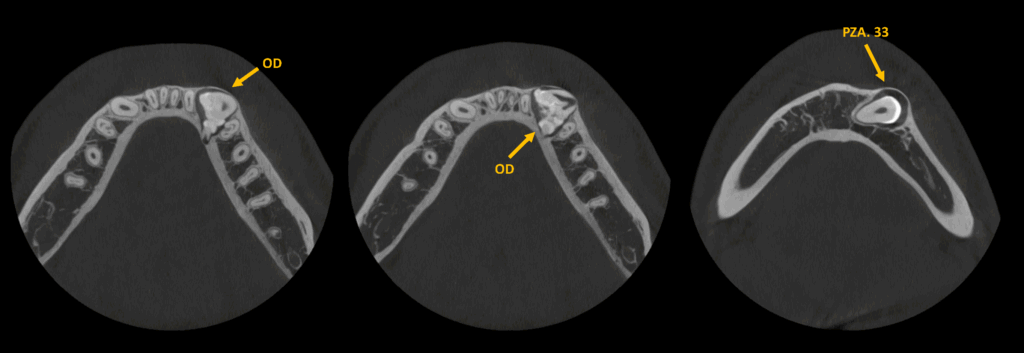

Asimismo, en el maxilar inferior se observa una imagen hiperdensa (OD) de densidad dentaria delimitada por un halo isodenso, ubicada entre las raíces de las piezas 34 y 32, que se extiende hacia las regiones linguales de las piezas 35 y 42.

Esta lesión ocasiona la impactación de la pieza 33 y genera expansión de la cortical ósea vestibular.

CORTES AXIALES